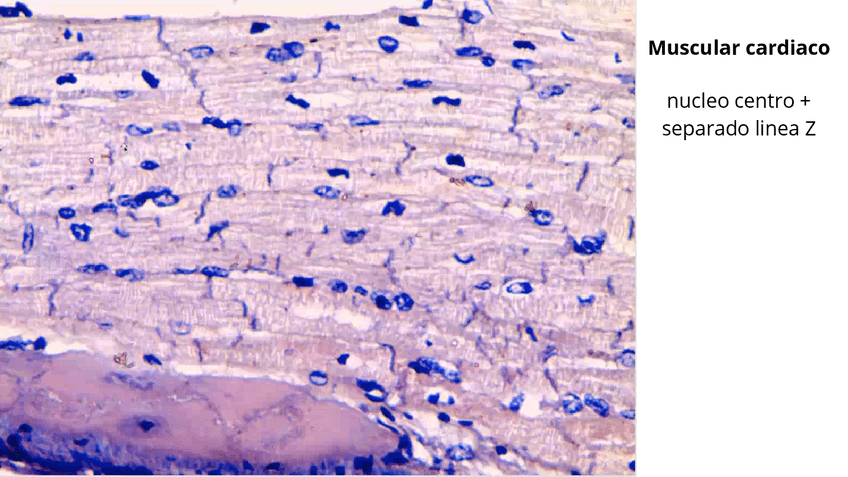

He publicado nuevos apuntes de 1º Histología: T4-histo-Muscular.pdf

T8.TEJIDO-MUSCULAR.pdf